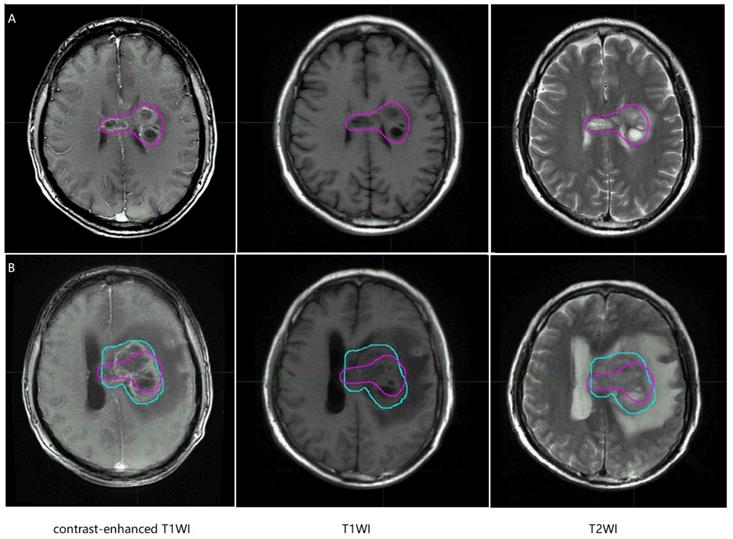

In the MR images of glioma patients, we delineated the gross tumor volume and recurrence tumor volume according to the regular MR images. As showed in Figure 8 and Figure 9, we tried to find the radiomics signature of tumor region without the peritumoral edema region.

Figure 8

Representative non-recurrence patient's regular brain MRI images, the purple line represents gross tumor volume. T1WI, T1 weighted image; T2WI, T2 weighted image.

J Cancer Image